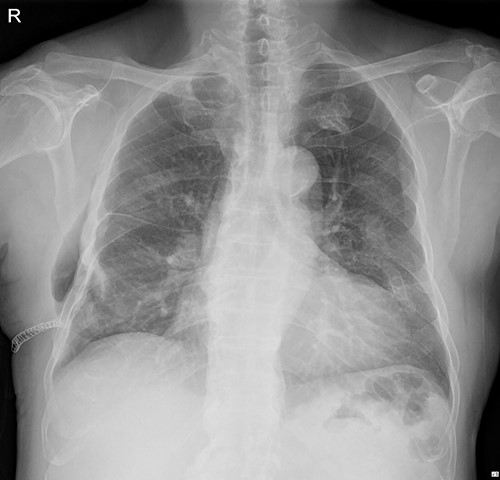

The submuscular emphysema, however, was increased in size, and the patient was eventually re-hospitalized. A small incision was made beneath the surgical wound under local anesthesia, and a 10 FR thoracic drainage catheter was carefully placed into the submuscular layer (Fig. 4.). Under 2 L of oxygen supplement, the submuscular emphysema gradually decreased over several days, and the patient was finally discharged on hospital Day 6 (Fig. 5). Since his last readmission, there have not been any more complications.

Chest X-ray after applying a 10 FR drainage thoracic catheter into the submuscular layer (11 March 2022).